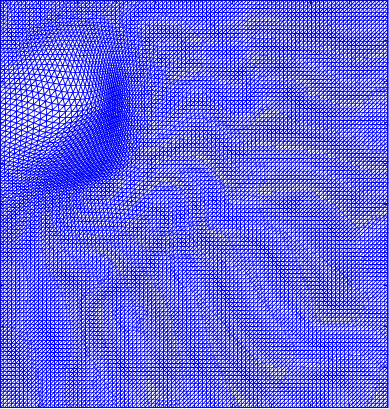

Figure 4 shows the visualisation of Figure 3 mappings in the form of grids. Let and be the Beltrami coefficients of the registration maps from the reference frame to the ground truth frame in Figure 3(a) and the perturbed frame in Figure 3(b) respectively. Figure 4(a) shows the mapping associated to Beltrami coefficient , and Fig 4(b) shows the mapping associated to BC . From Figure 4(c) and Fig 4(d), we can see that our method successfully restored the normal and abnormal deformation. Figure 4 serves as evidence that our decomposition is meaningful, in the sense that our method does not blindly return a Beltrami Descriptor with certain periodicity, but the decomposed descriptor does carry our desired information to recover the deformation to a large extent.